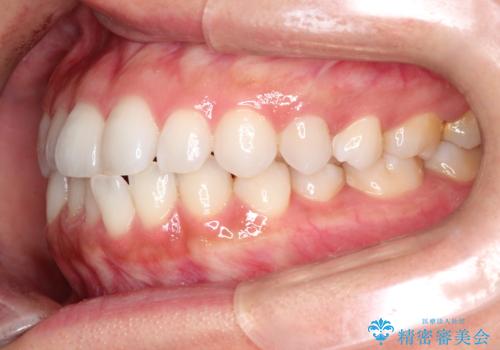

前歯の叢生を非抜歯で改善|インビザライン+IPR・遠心移動・FIX保定

- 前歯部のガタガタ(叢生)を非抜歯で改善するため、インビザラインによるマウスピース矯正を計画しました。抜歯は行わず、歯間をわずかに削るIPR(ディスキング)と奥歯を後方に移動させる遠心移動を併用して、歯を並べるスペースを確保します。歯列が整った後は、FIXリテーナー(固定式保定装置)で後戻りを防止し、安定した歯並びを維持します。

歯を抜きたくないというご希望に応え、インビザラインを用いて非抜歯で歯列を整えました。前歯に必要なスペースを確保するため、歯間をわずかに削るIPRと奥歯を後方に移動する遠心移動を組み合わせました。これにより自然で美しい歯並びを実現。治療終了後は、歯の裏側に目立たないFIXリテーナーを装着し、歯列の後戻りを効果的に防ぎました。患者様は治療中も審美的にストレスなく過ごされ、満足度の高い結果を得られました。